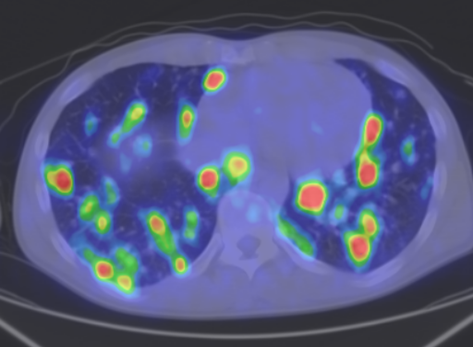

The most common clinical use of FDG-PET is in the form of whole-body scan, with oncologic indications. The majority of malignant tumors operate with higher energy consumption and show an increased glucose metabolism, consequently an increased uptake of FDG. The grade of malignancy is usually proportional to the rate of uptake. This method is useful in oncologic diagnostics, since it is capable to differentiate benign lesions from malignant ones. Whole-body PET imaging is capable to detect the primary tumor with local nodal metastases as well as distant metastatic lesions (staging) in one examination. (Figure 10.)

Test iframe

a

Image

b

c

d

10. Ewing’s sarcoma in the right humerus. Staging FDG PET-CT. PET Maximum Intensity Projection (MIP) image (a), transversal (b,c) and coronal (d) plane fused PET-CT images. Multiplex metastatic process with nodal, lung and bone involvement.